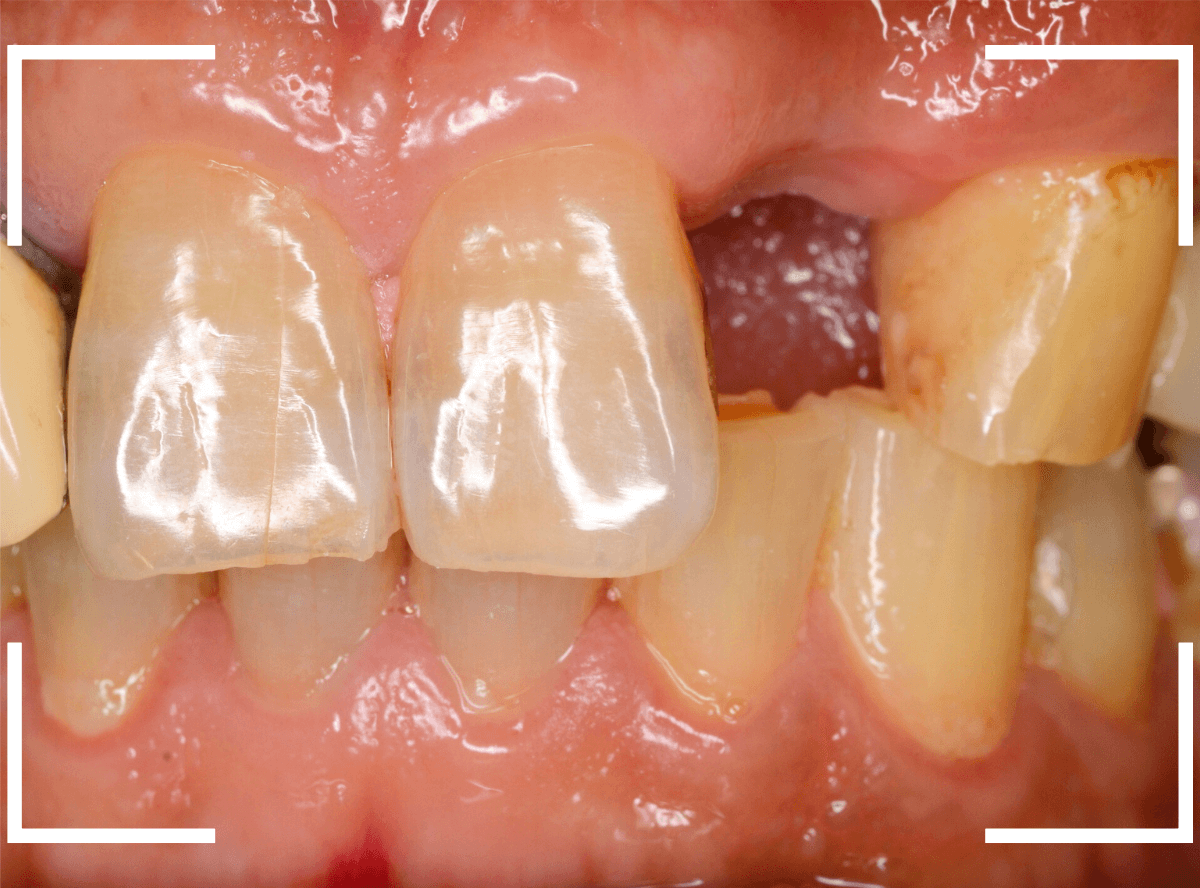

以前に上の前歯を抜歯された患者さんです。

抜歯後、都合によりしばらく入れ歯で経過観察していましたが、改めてインプラント治療をご希望されました。

インプラントset後の状況です。

審美的にも、満足いただける仕上がりになりましたが、現在の状況を維持するために治療後の定期メンテナンスが不可欠になります(インプラントに限りませんが)。